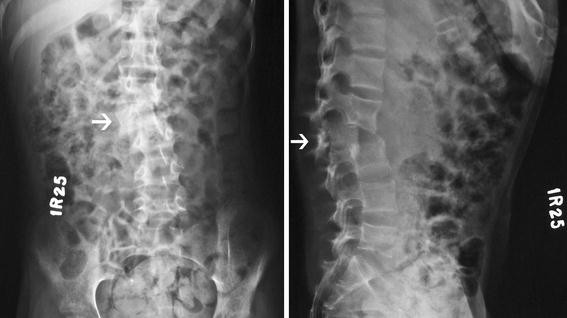

Lumbar posterior listhesis in 2021

Lumbar posterior listhesis picture This picture representes lumbar posterior listhesis.